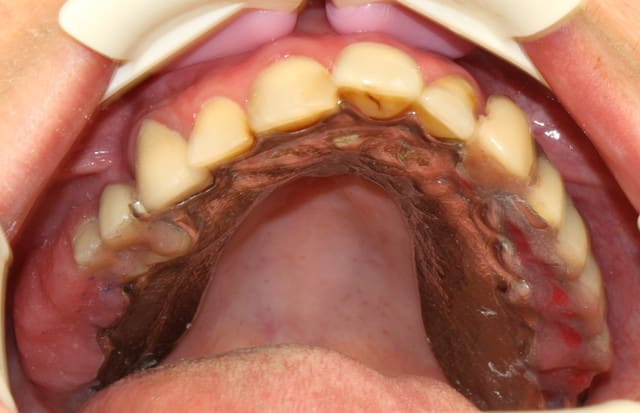

je continue l'entrainement :

voila Marc j'ai recadré!

Le sujet : ajuster un stellite après la pose des vis de cicatrisation sur 8 implants.

Rien de mirifique, juste un "bricolage" pour que la patient puisse manger.

le cadrage est bon...mais t'as un problème de flou de bougé (vitesse trop lente)

mais bien pour la dernière